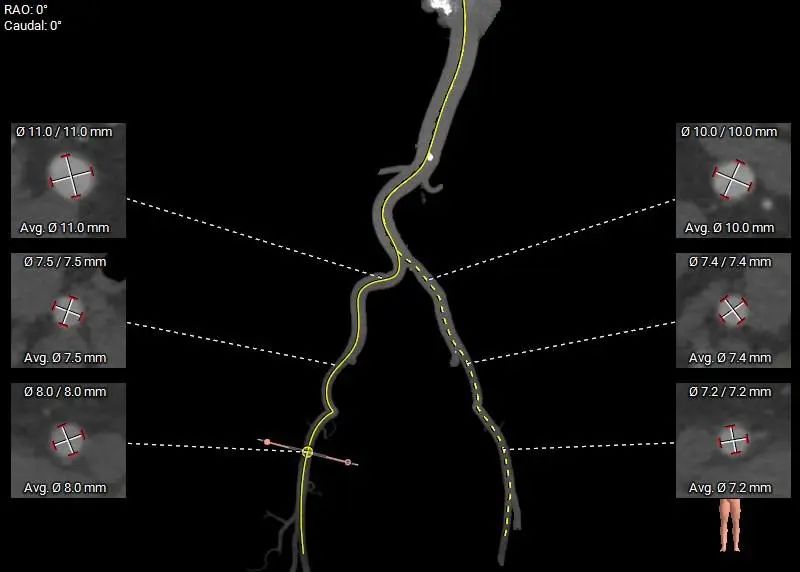

外周走行存在多处迂曲,腹主上端和左侧髂总动脉存在少量散在钙化斑,血管内径可,血管内壁存在钙化和不规则纤维增厚。

外周血管及主动脉弓解剖: